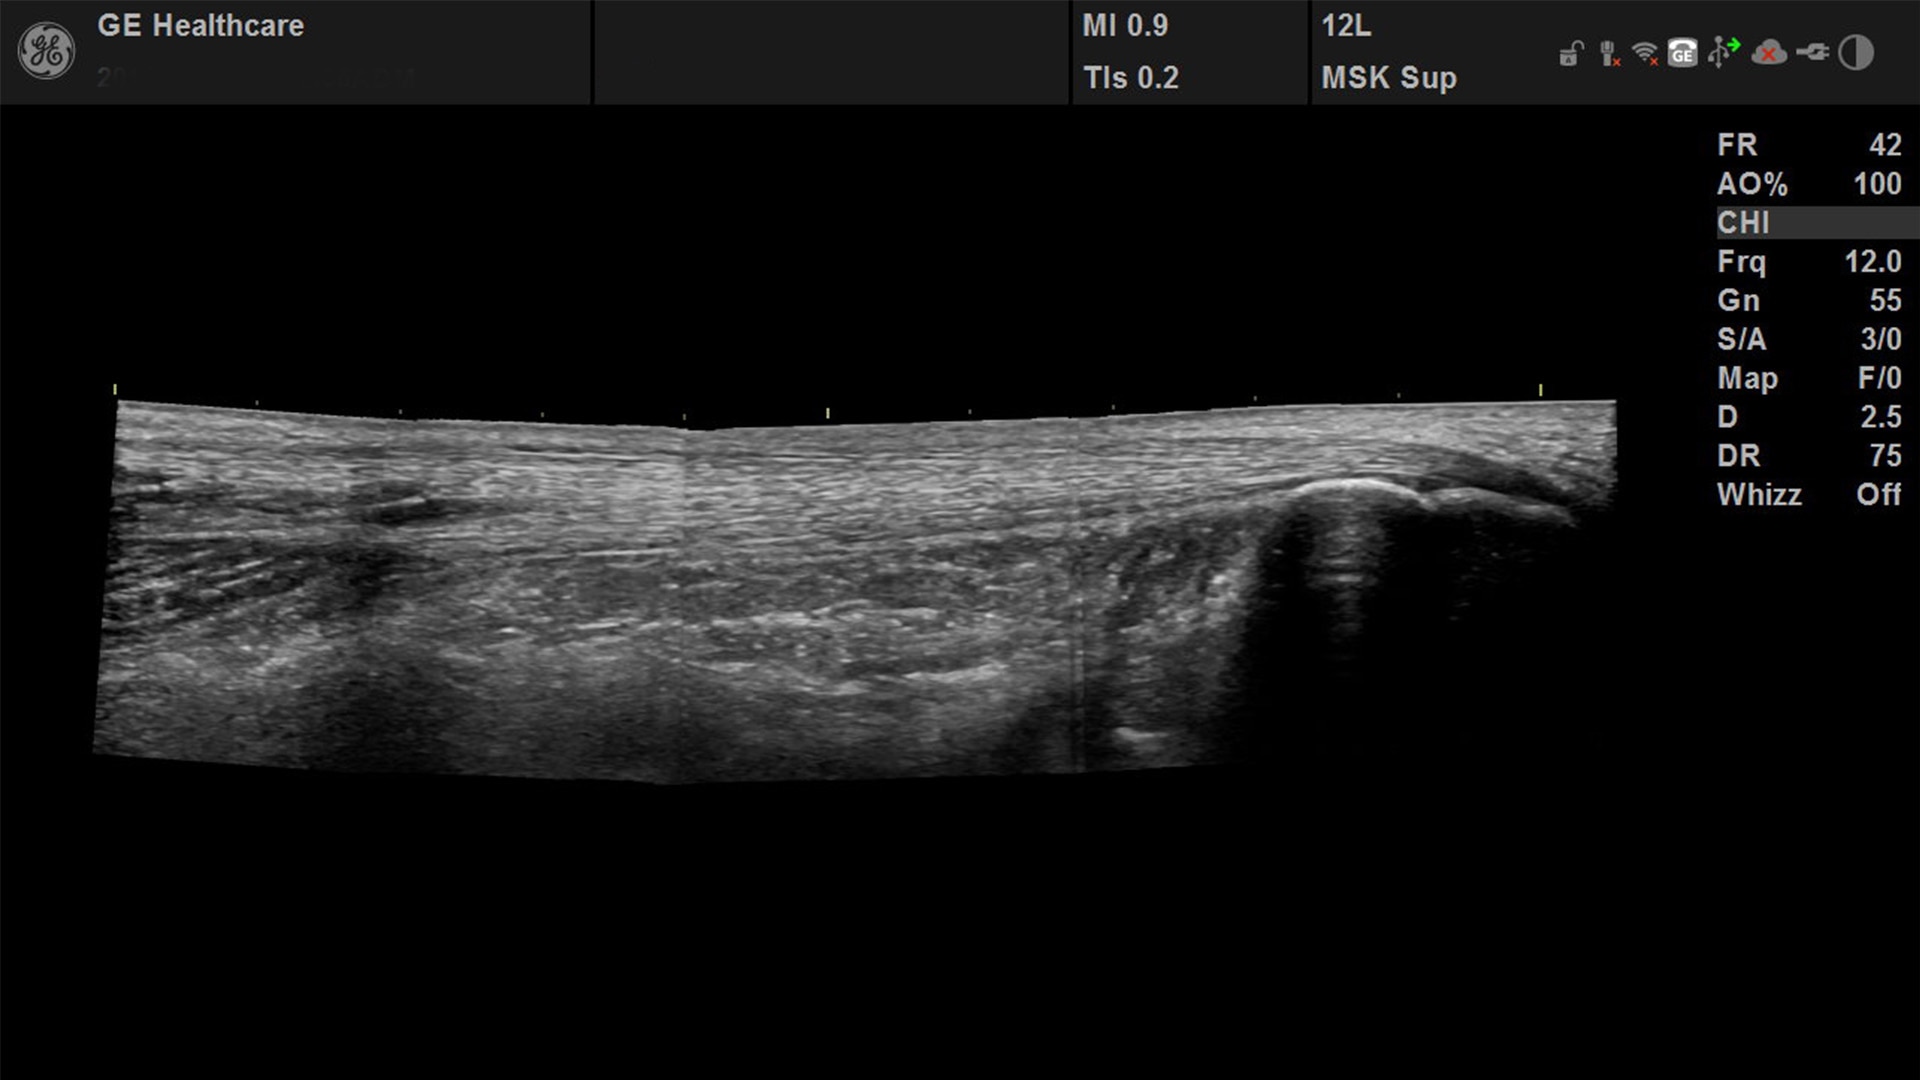

Suited for abdominal, small parts, cardiac, OB/GYN, vascular, and MSK exams

Versana Active features a wide range of advanced clinical applications and automated tools that simplify exams, streamline workflow, and enable fast, high-volume scanning to help you diagnose a wide spectrum of patient conditions.